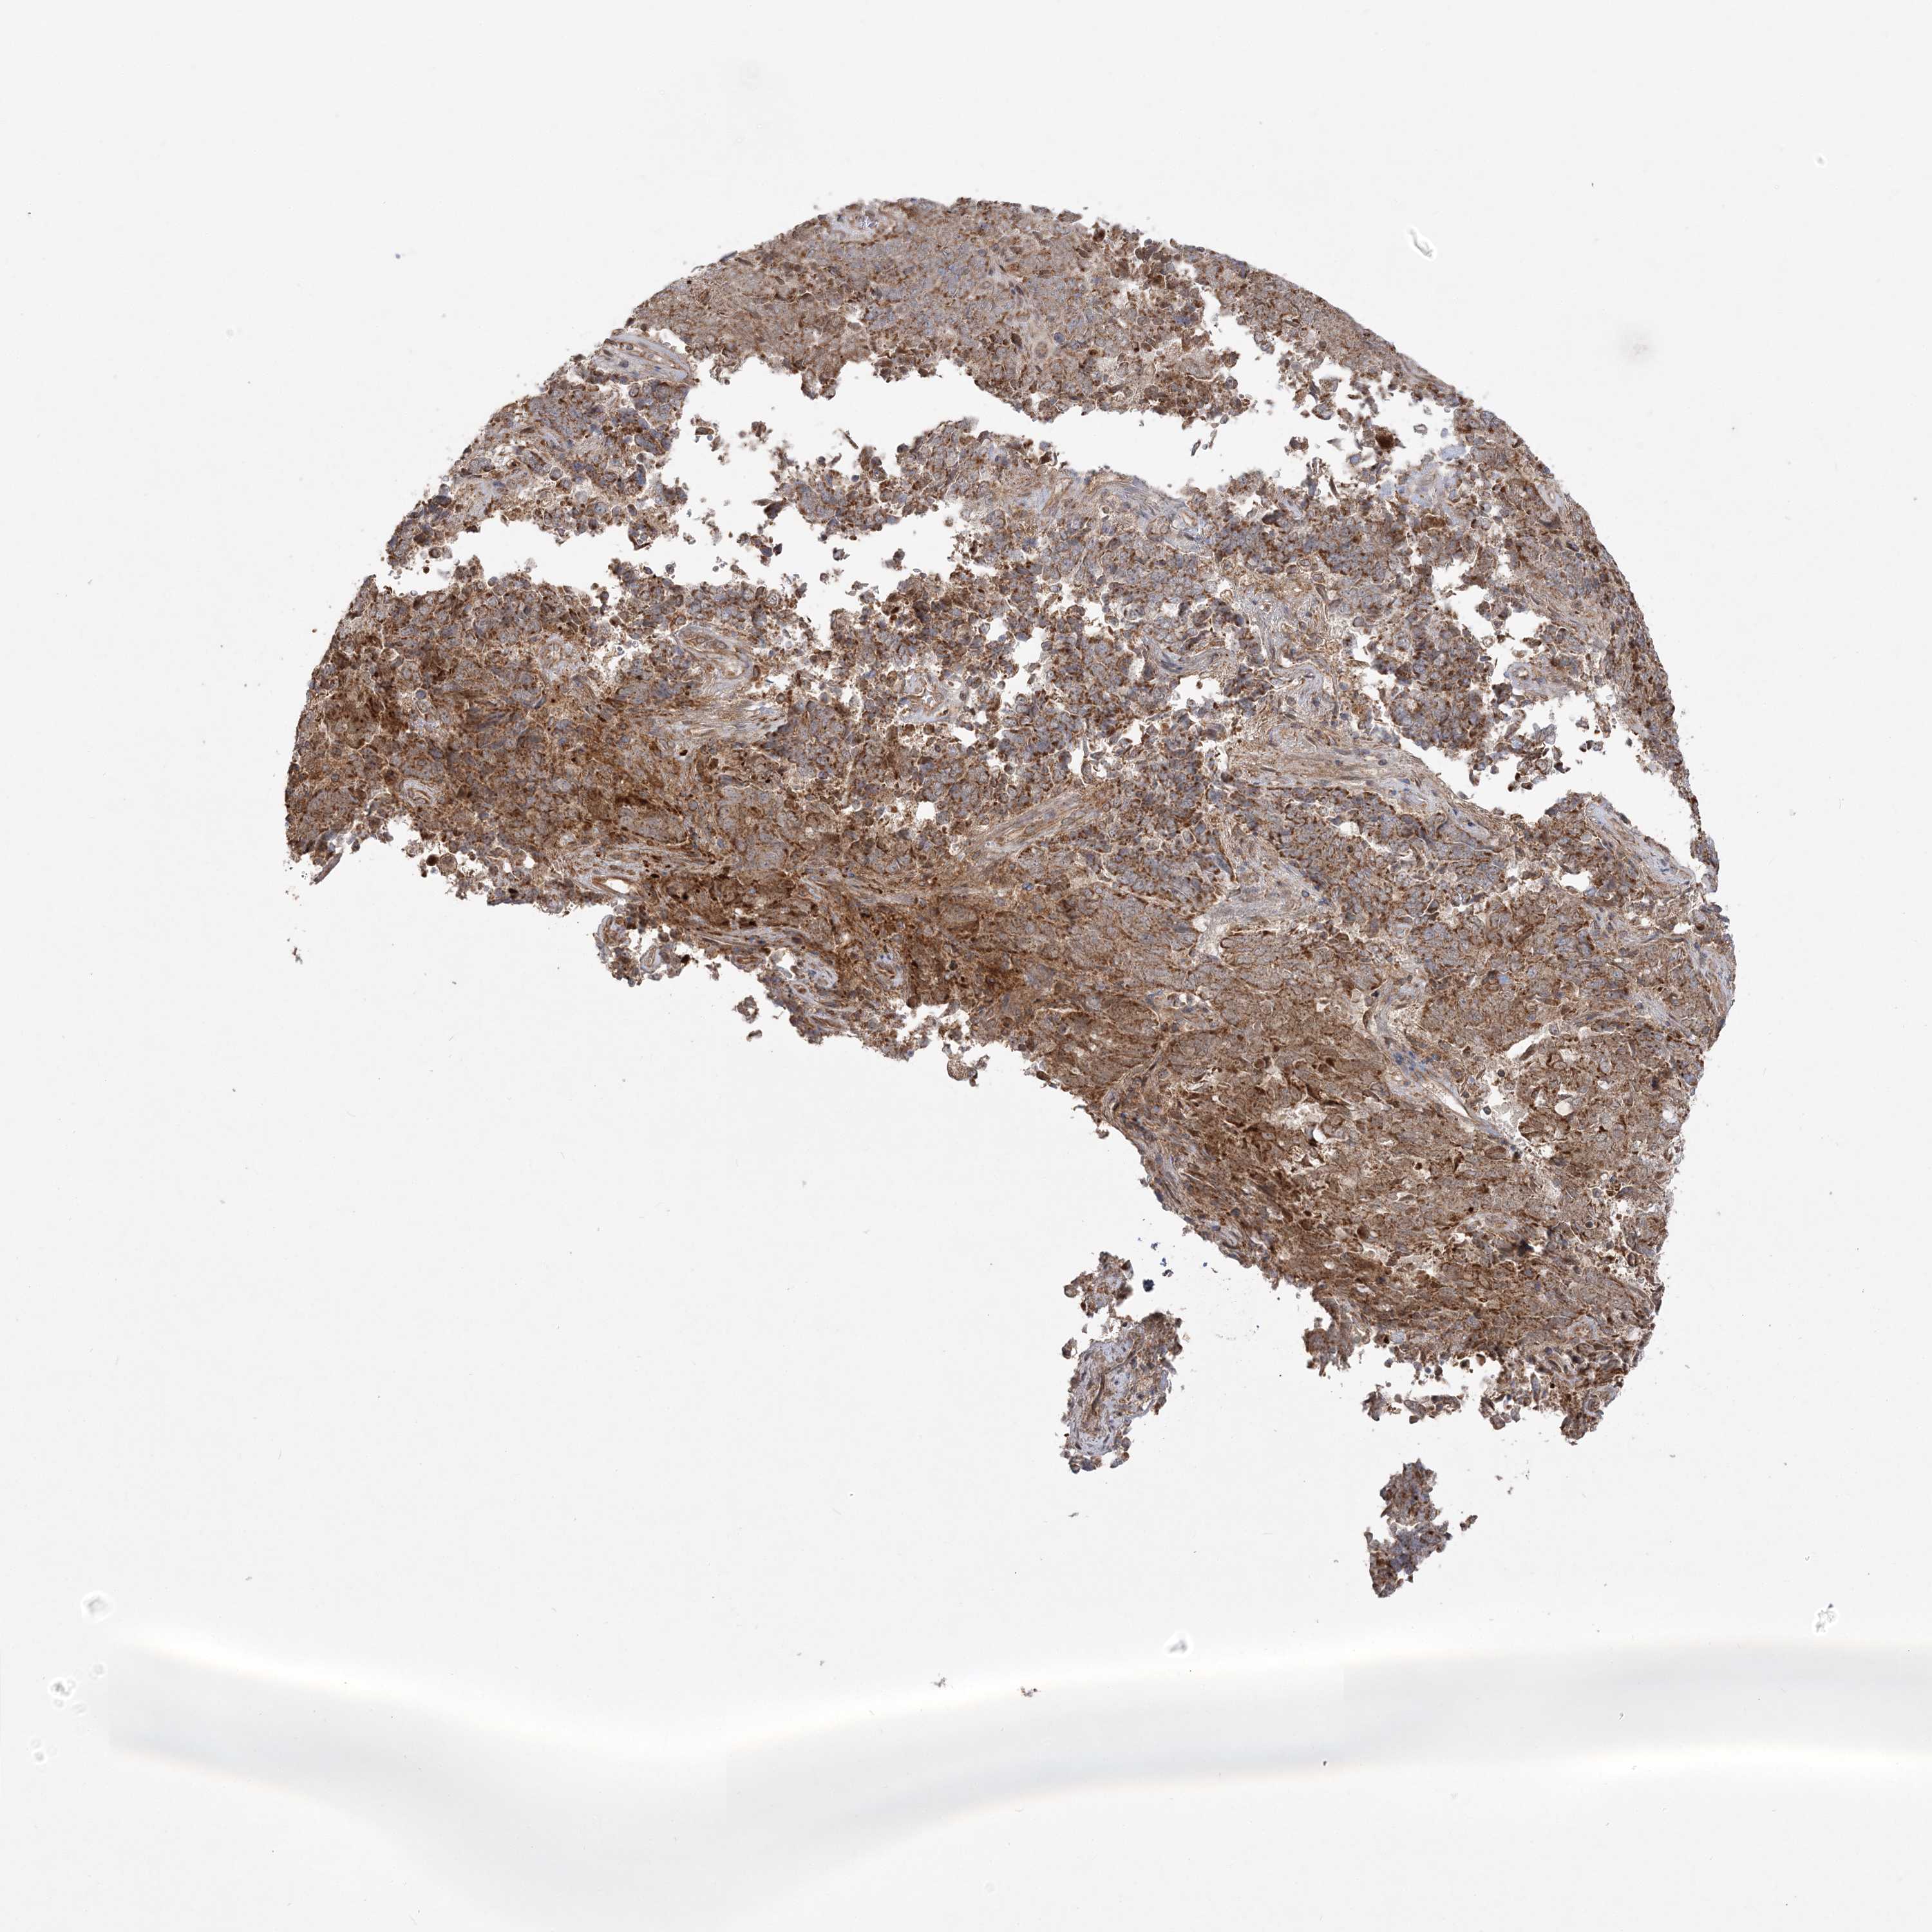

ENDOMETRIAL CANCER - Protein expressioni

A mouse-over function shows sample information and annotation data. Click on an image to view it in a full screen mode. Samples can be filtered based on level of antibody staining by selecting one or several of the following categories: high, medium, low and not detected. The assay and annotation is described here.

Note that samples used for immunohistochemistry by the Human Protein Atlas do not correspond to samples in the TCGA dataset.

Antibody stainingi

Antibody staining in the annotated cell types in the current human tissue is reported as not detected, low, medium, or high, based on conventional immunohistochemistry profiling in selected tissues. This score is based on the combination of the staining intensity and fraction of stained cells.

Each image is clickable and will lead to virtual microscopy that enables deeper exploration of all samples and also displays staining intensity scores, fraction scores and subcellular localization as well as patient and tissue information for each sample.

Antibody HPA036560

Antibody HPA036561

Staining

High

Medium

Low

Not detected

Intensity

Strong

Moderate

Weak

Negative

Quantity

>75%

75%-25%

<25%

None

Location

Nuclear

Cytoplasmic/membranous

Cytoplasmic/membranous,nuclear

Adenocarcinoma, NOS